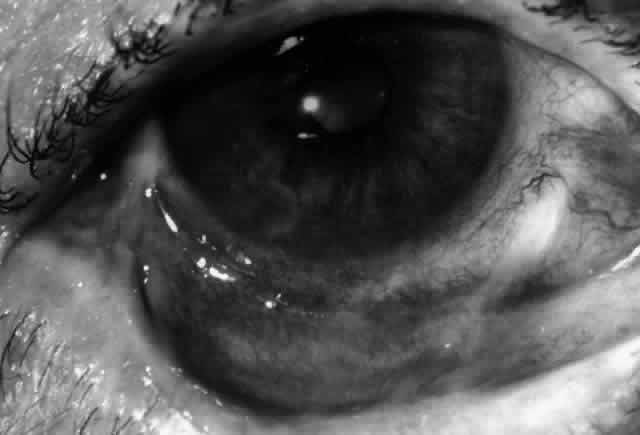

Clinically, the ocular disease in cicatricial pemphigoid (OCP) may present unilaterally in the form of a chronic, recurrent catarrhal conjunctivitis, but it eventually becomes bilateral. Subepithelial fibrosis is characteristic of stage 1 of OCP (Fig. 7). Stage 2 shows fornix foreshortening (Fig. 8), and symblepharon formation is the hallmark of stage 3 (Fig. 9). Stage 4, end-stage disease, is characterized by ankyloblepharon and surface keratinization (Fig. 10). Obstruction of the lacrimal ductules and meibomian gland ducts eventually produces an unstable tear film and progressive sicca syndrome, but it is to be emphasized that OCP is not a dry-eye syndrome until late in the disease course.20 Trichiasis and entropion occur because of the subepithelial fibrosis, with eventual keratopathy, corneal neovascularization, and corneal ulceration and scarring.20

Fig. 8. Stage 2 cicatricial pemphigoid, with fornix foreshortening and subepithelial fibrosis without frank symblepharon formation.